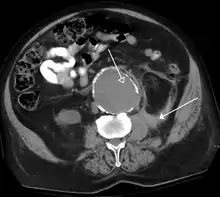

The most common technique is to perform portal venous phase imaging in the abdomen and pelvis (approximately 60–90 seconds after contrast administration, figure 2). This results in near optimal contrast opacification of the majority of the solid abdominal organs and it is used for a wide variety of indications: nonspecific abdominal pain; hernia; infection; masses (with a few exceptions such as hypervascular, renal, and some hepatic tumors); and in most follow-up examinations. As a general rule, this single phase is adequate unless there is a specific clinical indication that has been shown to benefit from other phases.

- FIGURE 2. Contrast enhanced CT demonstrating parenchymal enhancement of the intra-abdominal organs in the portal venous phase (axial left, coronal reformat right).